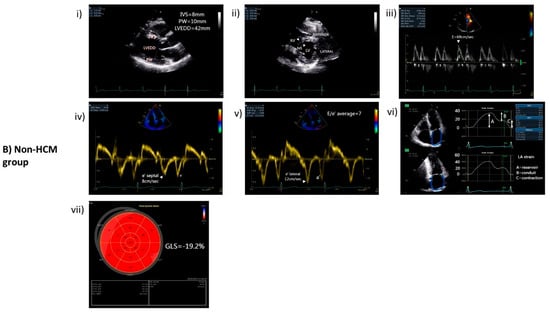

| HCM (n = 46) | Non-HCM (n = 27) | Significance (p-Value) | |

|---|---|---|---|

| LVEDD (mm) | 47 (±7) | 47 (±4) | 0.893 |

| LVESD (mm) | 30 (±6) | 31 (±4) | 0.684 |

| IVS (mm) | 18 (±4) | 10 (±2) | <0.001 |

| PW (mm) | 11 (±2) | 9 (±1) | 0.005 |

| MWT (mm) | 19 (±3) | 10 (±2) | <0.001 |

| LV mass index (g/m2) | 137 (±30) | 77 (±23) | <0.001 |

| Location of asymmetric LV hypertrophy | |||

| IVS | 39 (84%) | - | |

| Apex | 4 (9%) | - | |

| Mixed | 3 (7%) | - | |

| LVOTO (mmHg) | 14 (30%) 61 mmHg ± 35 | - | |

| LVEF (%) | 58 (±8) | 60 (±4) | 0.435 |

| GLS (%) | −14 (±6) | −20 (±2) | <0.001 |

| LA diameter (mm) | 47 (±7) | 39 (±5) | <0.001 |

| LA volume index (mL/m2) | 51(±18) | 29 (±10) | <0.001 |

| E/e’ratio | 13 (±7) | 8 (±3) | <0.001 |

| LA strain (reservoir) | 20 (±7) | 31 (±9) | <0.001 |

| LA strain (conduit) | −10 (±5) | −15 (±5) | 0.001 |

| LA strain (contraction) | −10 (±5) | −16 (±6) | <0.001 |